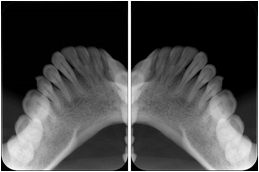

2. A patient requests cosmetic surgery to enhance their facial appearance. The case requires consultation between an orthodontist in New York and an oral surgeon in California. The cephalometric series of 2D projections constructed from a volumetric CT data set that is used for the discussion is arranged by a Structured Display for transfer between the two practitioners.

Cephalometric Series Structured Display

Figure OO-2. Cephalometric Series Structured Display